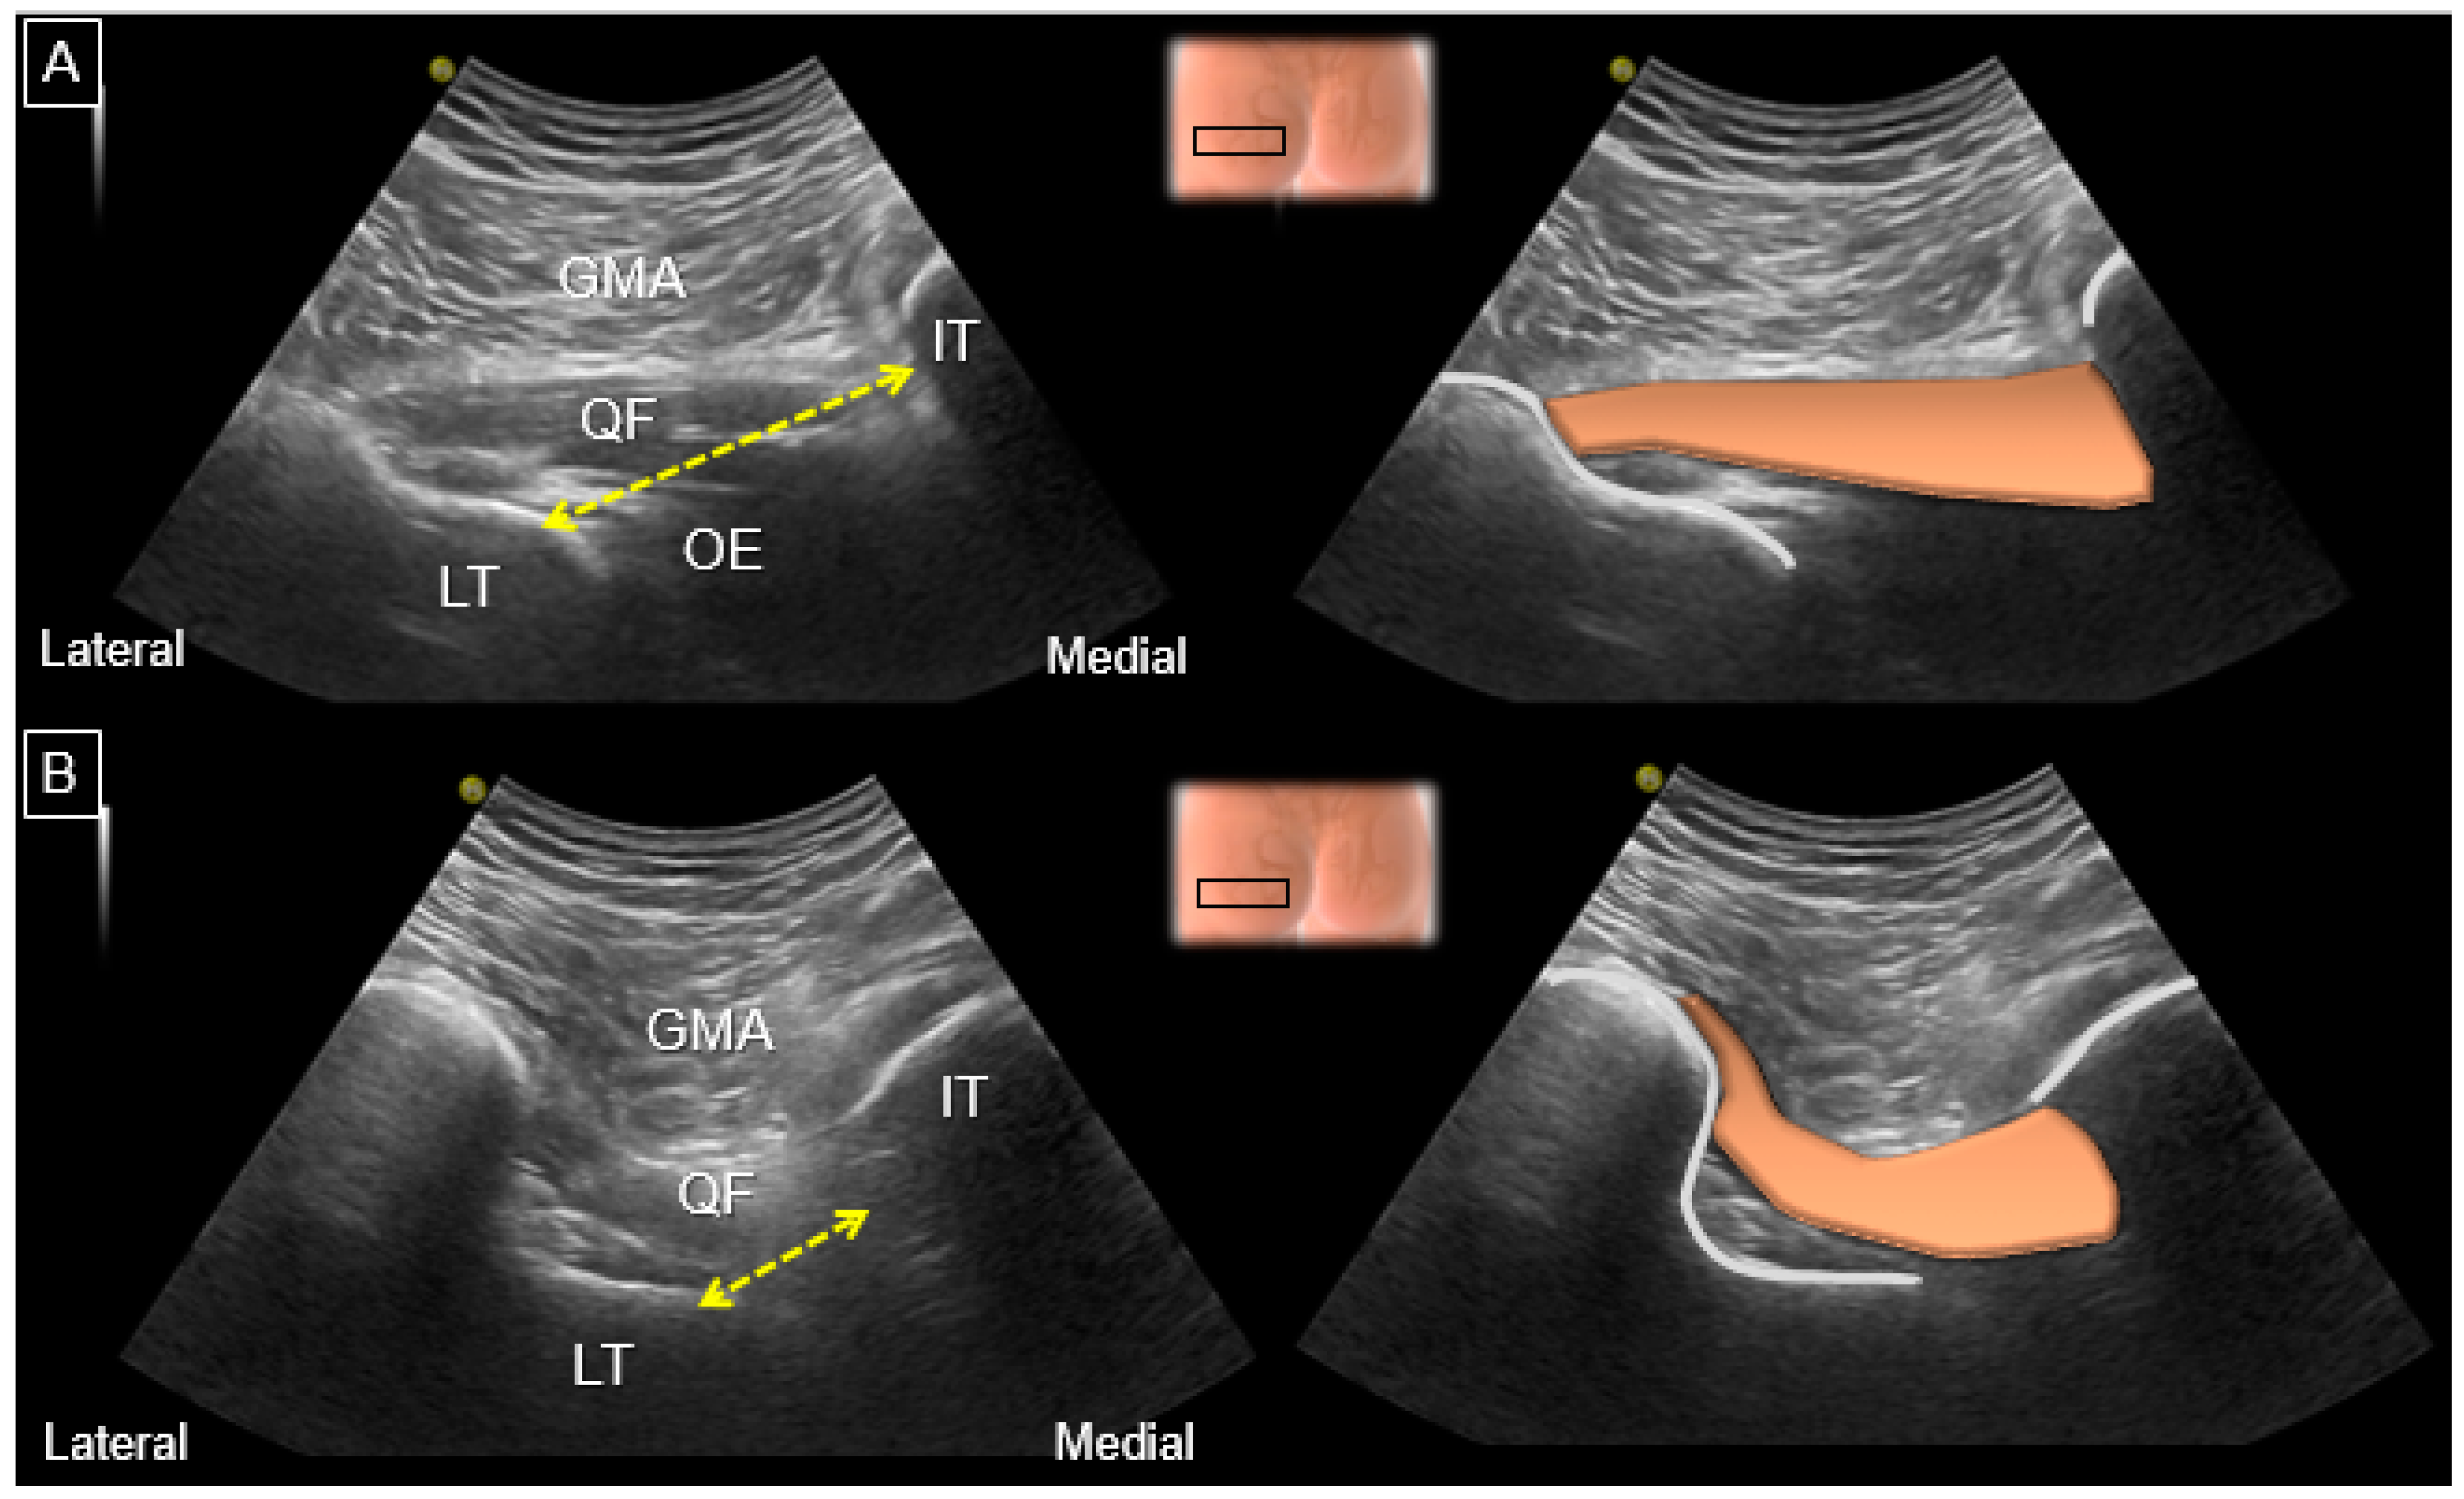

8. Dynamic Ultrasound Evaluation